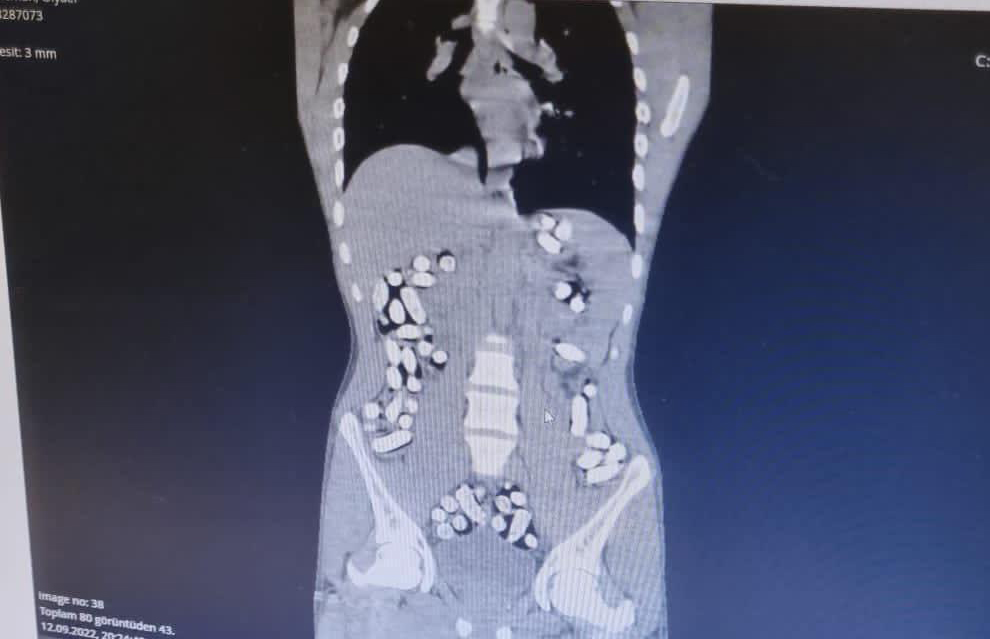

Çekilen röntgen filmlerinde şüphelilerin vücutlarında 62 kapsül eroin ve 210 kapsül afyon sakızı olduğu tespit edildi.

İç organlarının her tarafına yayıldığı belirlendi

Röntgen çekimlerinde uyuşturucu kapsüllerinin şüphelilerin neredeyse iç organlarının her tarafına yayıldığı belirlendi.

Doktor ve polis, vücutta tek seferde bu kadar yüklü miktarda uyuşturucu görmenin şaşkınlığını yaşadı.